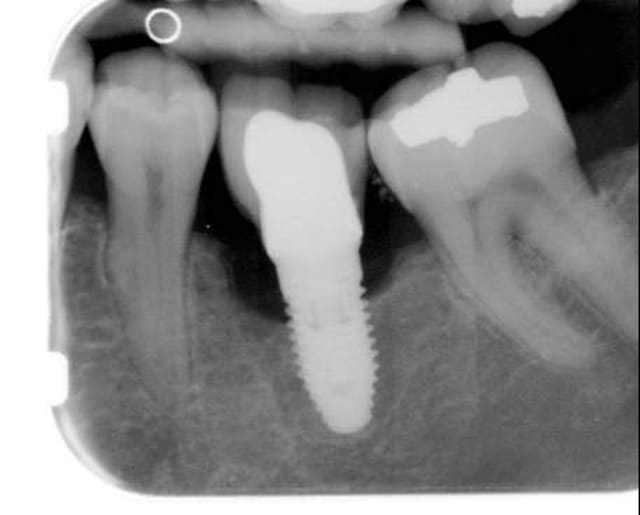

Vu une patiente sypa qui vient d'emmenager dans le coin et qui a perdu une couronne sur implant. L'implant posé il y a six moix, Mise charge 2 mois après, et je vois ça à la radio, plus une gencive assez inflammatoire. Je lui annonce le plus délicatement possible (pas facile) qu'il y a peut-être un petit souci, mais que seule sa CD qui a posé l'implant peut comparer avec l'origine, et que je vais donc lui envoyer les radios par mail. Qu'en pensez-vous? Je ne sais pas quoi faire ni quoi dire au confrère pour ne pas être indélicat. La patiente a priori sympa et pas revendicative du tout commençait à paniquer, je l'ai rassuré en lui disant qu'il fallait l'avis de celle qui avait posé pour voir s'il y avait une évolution ou pas, mais je suis assez gêné!!

Hummm!!!, çà sent la péri-implantite...

en effet il y a problème...et puis mise en charge à 2 mois...encore un(e) qui a écouté les commerciaux et pas révisé la physiologie osseuse...3 mois, une cicat osseuse complète...pas 2...et en dehors de toute complication de cicat...

là, à mon avis c'est mal barré...y a de la dépose dans l'air...

Dans le bouquin de Davarpanah, 2ème édition, page 48, les clichés de péri-implantite ressemblent bien à celui-là.

ça pourrait être aussi une cratérisation due à des forces trop importantes au niveau du col de l'implant lors de la mise en place de celui ci dans un os dense.

C'est bien pour ça que je m'attardais sur le modèle de l'implant car je pense qu'il pourrait s'agir d'une cratérisation dûe à des compressions excessives lors de la pose... fréquent avec un tapered aussi conique.

oui çà peut être çà aussi...sur du Nobel..(jamais vu ce cas sur du Zimmer)...mais çà change rien au problème de cet implant...pour moi, y va pas très bien...et la mise en charge précoce n'a sûrement pas arrangé les choses...

si l'implant a été posé avec le col non enfui, y'a une perte d'une à deux spires... et alors ??? Elle a peut-être eu lieu au cours des 6 première semaines. A partir de 1,5 mm on parle d'échec; pas avant. Comme on sait pas comment c'était à la pose......

c'est pas sur une radio que l'on fait un diagnostic les enfants !!!

Je pense aussi que c'est un Tapered Nobel

mais on sait pas comment c'était avant, au moment de la pose et au moment de la mise en charge.

alors facile de lancer: péi-mplantite; mal barré.......

Un peu de recul clinique please.

D'abord la gencive est moche et inflammatoire, ensuite j'ai demandé à la consoeur si elle voulait bien m'adresser la radio de départ, on pourrait comparer ce serait intéressant.